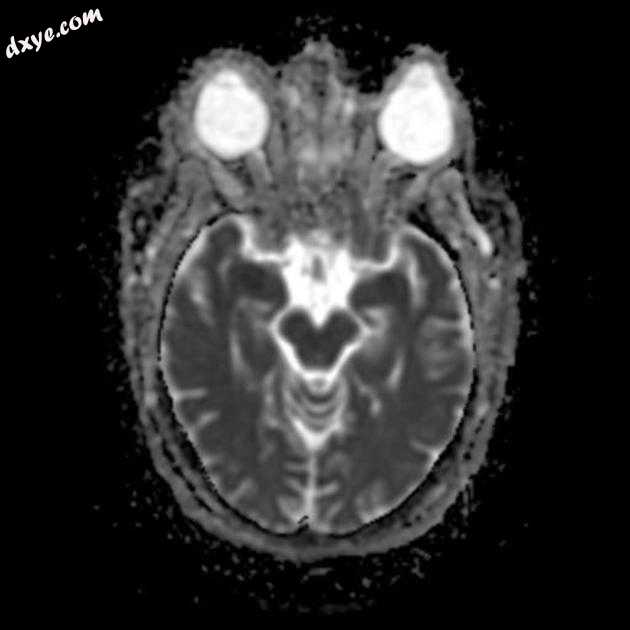

Axial DWI

MRI 序列显示左侧大脑中动脉 (MCA) 区域分布中的弥散受限区域,在 FLAIR 序列上不可见。在 GE 序列上没有看到出血性转化。 MRA 3D-TOF 显示左侧大脑中动脉完全闭塞。

早期超急性大脑中动脉 (MCA) 区域梗死的 MRI 特征。